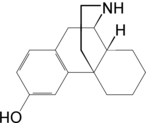

The pharmacodynamic response to an opioid depends upon the receptor to which it binds, its affinity for that receptor, and whether the opioid is an agonist or an antagonist. For example, the supraspinal analgesic properties of the opioid agonist morphine are mediated by activation of the μ1 receptor; respiratory depression and physical dependence by the μ2 receptor; and sedation and spinal analgesia by the κ receptor. Each group of opioid receptors elicits a distinct set of neurological responses, with the receptor subtypes (such as μ1 and μ2 for example) providing even more [measurably] specific responses. Unique to each opioid is its distinct binding affinity to the various classes of opioid receptors (e.g. the μ, κ, and δ opioid receptors are activated at different magnitudes according to the specific receptor binding affinities of the opioid). For example, the opiate alkaloid morphine exhibits high-affinity binding to the μ-opioid receptor, while ketazocine exhibits high affinity to ĸ receptors. It is this combinatorial mechanism that allows for such a wide class of opioids and molecular designs to exist, each with its own unique effect profile. Their individual molecular structure is also responsible for their different duration of action, whereby metabolic breakdown (such as N-dealkylation) is responsible for opioid metabolism.

Several semi-synthetic opioids were developed in Germany in the 1910s. The first, oxymorphone, was synthesized from thebaine, an opioid alkaloid in opium poppies, in 1914.[228] Next, Martin Freund and Edmund Speyer developed oxycodone, also from thebaine, at the University of Frankfurt in 1916.[229] In 1920, hydrocodone was prepared by Carl Mannich and Helene Löwenheim, deriving it from codeine. In 1924, hydromorphone was synthesized by adding hydrogen to morphine. Etorphine was synthesized in 1960, from the oripavine in opium poppy straw. Buprenorphine was discovered in 1972.[228]